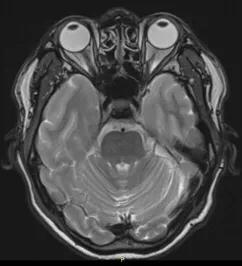

再简单说说MRI,磁共振成像。MRI要比CT复杂得多。在磁共振成像发明的初期,科学家们将它命名为核磁共振成像(NMRI),由于有一个“核”字,极容易导致人们将其与核反应、放射性核素联系到一块儿。其实是完全不同的概念,两者风马牛不相及。工作中,很多的朋友、患者问到这个问题,解释了无数遍。其实,简单的想一想,如果真有核辐射损害,怎么可以用于大众检查身体呢?这种误解,在国内外均发生过。后来,国际上统一命名,英文是Magnetic Resonance Imaging,简称MRI。这就是其名称的来源。国内呢,也把“核磁共振”改成了“磁共振”,以免误解。直到今天,依然有老一辈的人叫做“核磁共振”,其实不用担心。那么,磁共振MRI是怎样成像的呢?说起来十分复杂,需要专门学习,是物理学和计算机的科学。简单地说,将人体置于一个静磁场中,我们身体细胞的原子核就会按照静磁场的方向有顺序的排队;此时,在检查部位(比如脑部)发射电磁脉冲(波长数米),这些排好队的原子就会发生偏转,将电磁脉冲停止以后,脑部原子核就会发生共振现象,即昌盛共振信号。此时用信号接收器接受信号,并经过放大、数模转换(与CT雷同),就会得到MRI图像了。从其原理可以看出,除了磁场与脉冲以外,无任何外加因素,对人体不产生危害,孕妇、婴幼儿都可以行MRI检查的,十分安全。自上世纪80年代起,MRI已经广泛运用了40年,时间验证是最可靠的。至于静磁场的场强、电磁脉冲对人体是否有影响,作者将在以后章节阐述。

正常脑MRI图像